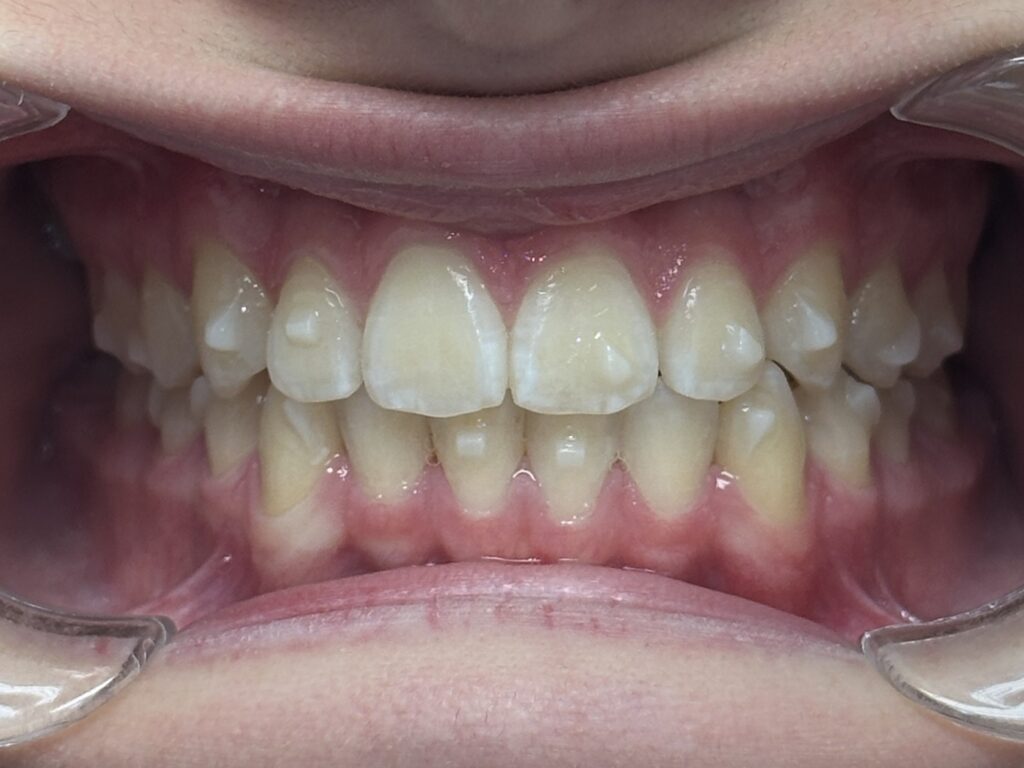

Efekty leczenia Invisalign®, czyli wyprostowane i prawidłowo ustawione w łuku zęby są osiągalne średnio o rok szybciej w porównaniu do klasycznej ortodoncji, pomimo tego, że nakładek nie nosi się całą dobę.

Leczenie Invisalign® może być nawet o 1/3 szybsze od ortodoncji aparatami stałymi i trwa średnio od 1 do 1,5 roku.

Czas leczenia Invisalign zależy od indywidualnych potrzeb pacjenta i stopnia korekty zębów.

Średni czas leczenia wynosi od 12 do 18 miesięcy, jednak w prostszych przypadkach może trwać krócej, a w bardziej skomplikowanych — dłużej.

Co ciekawe, leczenie niewidocznymi nakładkami Invisalign, które zdejmuje się na 2 godziny na dziennie, jest krótsze o 30% w porównaniu do leczenia aparatami naklejanymi na stałe (średnio od 1,5 do 2,5 roku),.